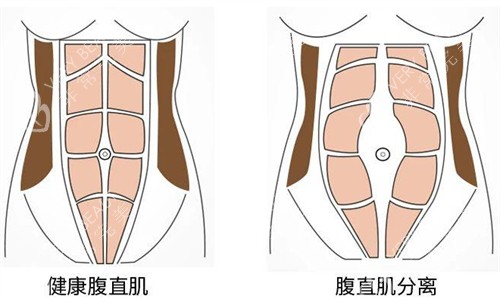

在上海进行腹直肌修复手术的总费用大约在18000-55000元左右,具体价格因手术方式、医生资质和术后护理方案而异。腹直肌修复手术是针对产后腹直肌分离或腹部肌肉松弛的正规医疗解决方案,下面我们将分类详细列出上海地区腹直肌修复手术的各项费用明细。

1. 手术复杂程度:轻度分离与重度分离修复价格差可达40%

需要特别说明的是,腹直肌修复手术属于个性化定制医疗服务,每位患者的具体情况不同,建议先做评估后再确定较终治疗方案。选择正规医疗机构和经验充足的正规医生是确保手术健康和结果的重要确保。术后严格遵循医嘱进行改善训练同样至关重要。